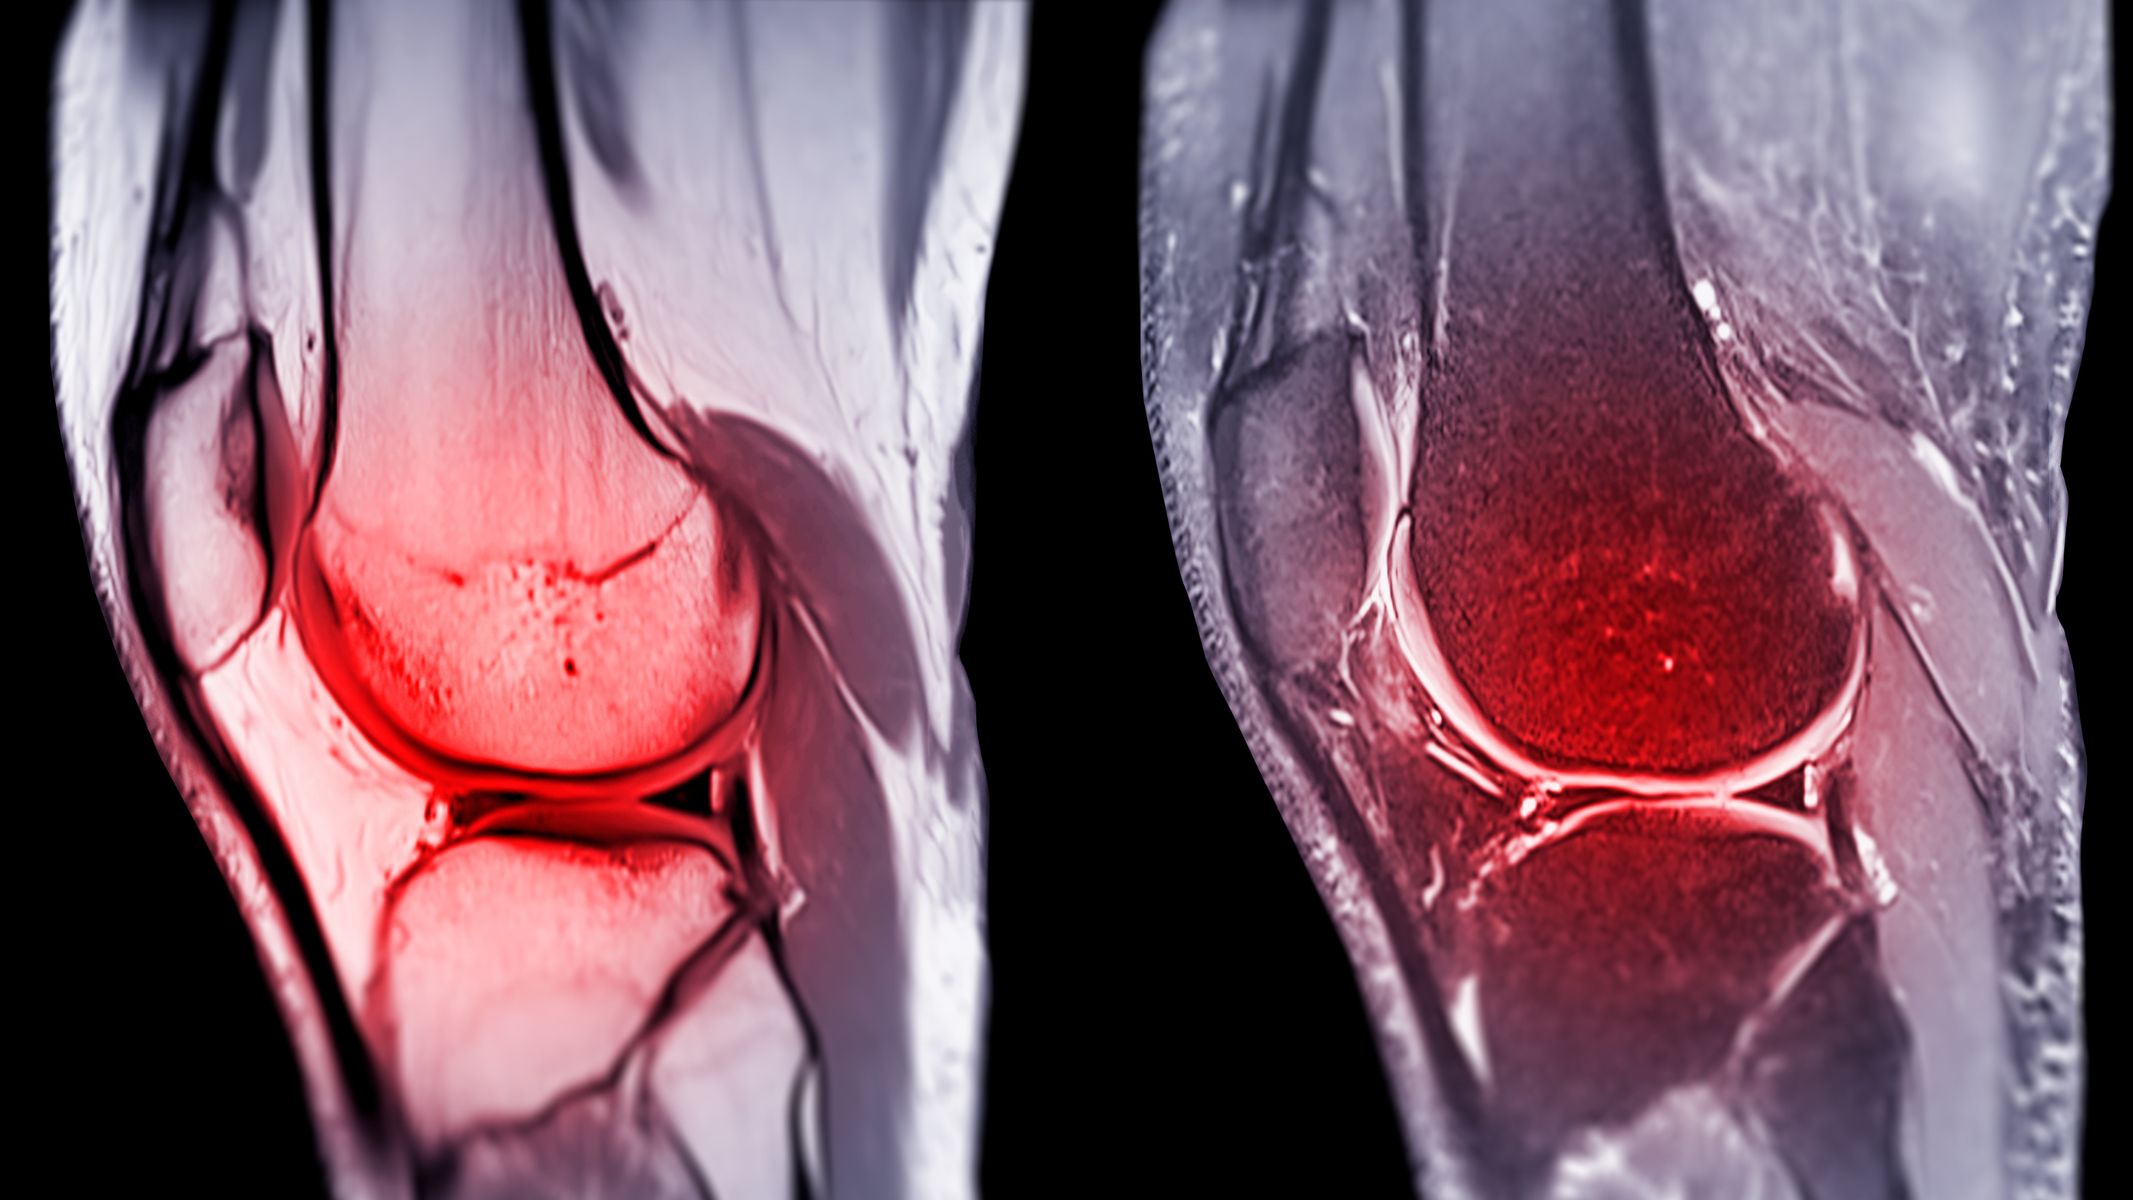

Phẫu thuật tái tạo dây chằng chéo trước là phương pháp điều trị phổ biến khi dây chằng trong khớp gối bị đứt hoặc tổn thương nghiêm trọng. Sau phẫu thuật, nhiều bệnh nhân nhận thấy đầu gối bị sưng và căng trong một thời gian nhất định. Đây là phản ứng tự nhiên của cơ thể khi mô và khớp trải qua can thiệp ngoại khoa.

Vì sao sau mổ dây chằng chéo trước khớp gối bị sưng?

Hiện tượng sưng sau phẫu thuật khớp gối là phản ứng sinh lý thường gặp. Tình trạng này xảy ra do nhiều yếu tố liên quan đến quá trình phẫu thuật và cơ chế hồi phục của cơ thể.